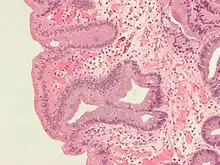

Intestinal metaplasia

The presence of goblet cells, called intestinal metaplasia, is necessary to make a diagnosis of Barrett's esophagus. This frequently occurs in the presence of other metaplastic columnar cells, but only the presence of goblet cells is diagnostic. The metaplasia is grossly visible through a gastroscope, but biopsy specimens must be examined under a microscope to determine whether cells are gastric or colonic in nature. Colonic metaplasia is usually identified by finding goblet cells in the epithelium and is necessary for the true diagnosis.

Many histologic mimics of Barrett's esophagus are known (i.e. goblet cells occurring in the transitional epithelium of normal esophageal submucosal gland ducts, "pseudogoblet cells" in which abundant foveolar [gastric] type mucin simulates the acid mucin true goblet cells). Assessment of relationship to submucosal glands and transitional-type epithelium with examination of multiple levels through the tissue may allow the pathologist to reliably distinguish between goblet cells of submucosal gland ducts and true Barrett's esophagus (specialized columnar metaplasia). The histochemical stain Alcian blue pH 2.5 is also frequently used to distinguish true intestinal-type mucins from their histologic mimics. Recently, immunohistochemical analysis with antibodies to CDX-2 (specific for mid and hindgut intestinal derivation) has also been used to identify true intestinal-type metaplastic cells. The protein AGR2 is elevated in Barrett's esophagus[17] and can be used as a biomarker for distinguishing Barrett epithelium from normal esophageal epithelium.[18]

The presence of intestinal metaplasia in Barrett's esophagus represents a marker for the progression of metaplasia towards dysplasia and eventually adenocarcinoma. This factor combined with two different immunohistochemical expression of p53, Her2 and p16 leads to two different genetic pathways that likely progress to dysplasia in Barrett's esophagus.[19] Also intestinal metaplastic cells can be positive for CK 7+/CK20-.[20]